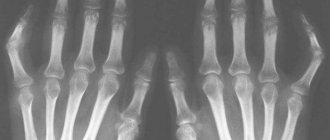

Инфекционные заболевания